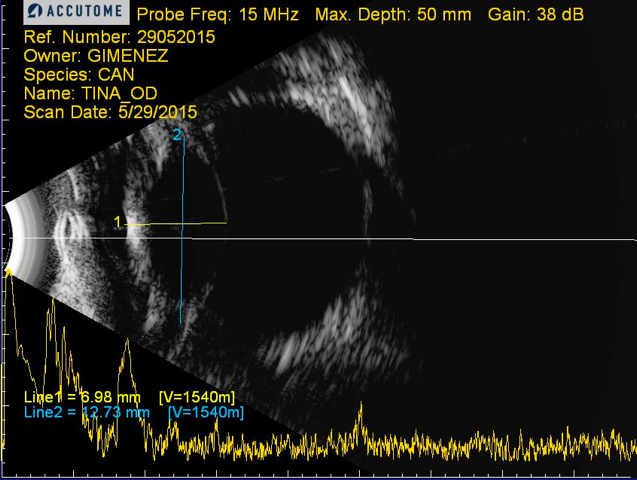

En el examen previo se comprobó que padecía una catarata diabética bilateral en un estado avanzado. Uno de sus ojos se había inflamado tanto que había causado la rotura de la cápsula del cristalino, y en el otro el cristalino empezaba a desprenderse.

El de Duque es un caso frecuente de catarata diabética que se desarrolla muy rápidamente. Su cirugía fue especialmente complicada, tal como puede apreciarse en el video que reproducimos al final del artículo.

Se realiza una cirugía de catarata bilateral en un perro mestizo de 12 años mediante facoemulsificación con implante de lente intraocular y anillo de tensión capsular en el ojo izquierdo. Por complicaciones intraquirúrgicas debido al estado avanzado de las cataratas diabéticas (rotura capsular ecuatorial), tuvo que realizarse un procedimiento intracapsular en el ojo derecho.